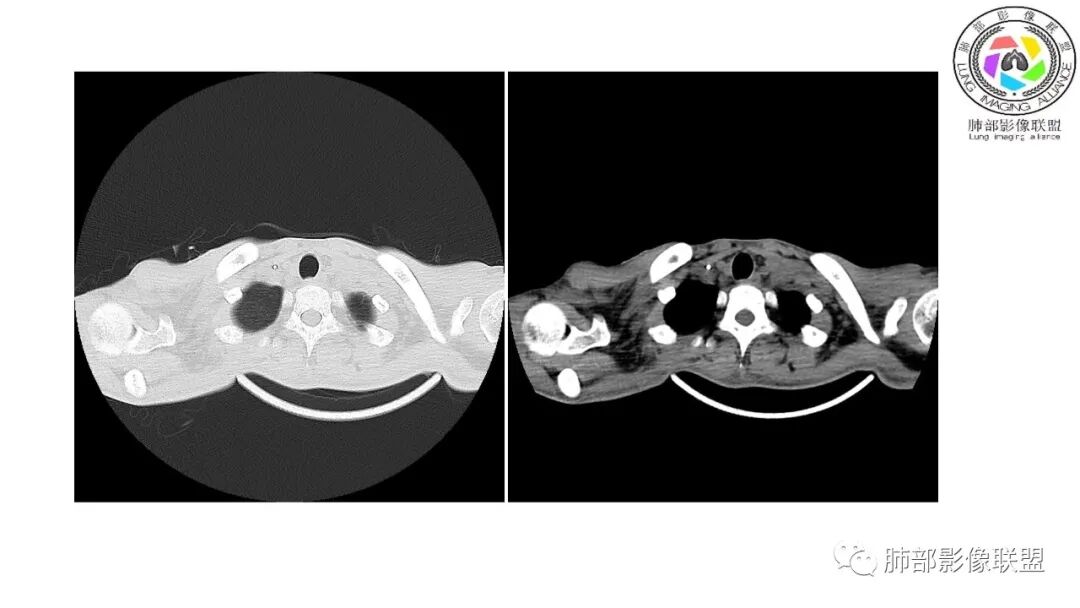

以下为2021-7-15日上腹部CT

影像与临床:1.青年男性,HlV阳性,颜面部皮疹(未提供皮疹图像)、发热(高热),实验室CRP、PCT高,T-Spot阴性。2.右肺下叶空洞结节,壁厚不均,边界清楚,其内线状影,未见液平及钙化,未见卫星灶,纵隔淋巴结增大,双侧腋窝见增大淋巴结。心腔内低密度提示贫血可能。肝脾影增大,未见结节影及块影。腹膜后见多发增大淋巴结。

综合分析:本例肺部影像学改变并不具有特征性,空洞性病灶须与多种疾病鉴别,但年轻HIV阳性患者,高热,皮疹,肝脾增大,纵隔、腋窝、腹膜后见多发增大淋巴结等都强烈提示马尔尼菲篮状菌感染的可能性。